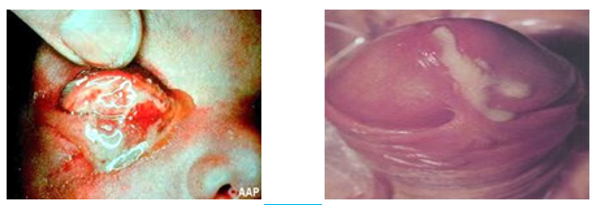

4. Ulkus Genital akibat LGV/Limfogranuloma Venereum

Merupakan infeksi menular seksual yang disebabkan oleh Chlamydia Trachomatis serovar L1,L2,L3. Manifestasinya akut dan kronis dan bervariasi. Nama lainnya tropical bubo. Limfo granuloma Venereum mengenai pembuluh limfe dan kelenjar limfe daerah genital, lipatan paha, anus dan rectum. Penularan terjadi mela lui kontak langsung dengan secret infeksius melalui berbagai macam hubungan seksual baik oral, genital maupun anal. LGV dapat terjadi bersama dengan infeksi menular seksual lain, seperti HIV. Penyakit ini bisa dialami siapa saja, tetapi lebih sering terjadi pada pria berusia 15–40 tahun yang aktif secara seksual atau melakukan hubungan seksual sesama jenis.

5. Limfoma Inguinale/Donovanosis

Granuloma inguinale bisa ditandai dengan munculnya benjolan merah berukur an kecil yang tidak terasa nyeri di area kelamin. Benjolan ini membesar secara perlahan, kemudian pecah dan membentuk luka. Jika dibiarkan tanpa pengobat an, luka ini dapat menjadi jaringan parut permanen. Borok tanpa rasa nyeri.Granuloma Inguinale atau Donovanosis disebabkan oleh bakteri Klebsiella granulomatis. Penyakit ini terjadi pada orang berusia umur antara 20-40 tahun yang aktif secara seksual. Perkembangan penyakit ini lambat, biasanya sekitar 17 hari setelah bakteri masuk kedalam tubuh hingga menimbulkan gejala dan diperlukan hingga 12 minggu sampai terdapat luka di kulit yang nyata. Tidak ditemukan gejala demam pada penyakit ini. Granuloma Inguinale sulit untuk dideteksi pada tahap awal. Penyakit ini disebabkan oleh bakteri Klebsiella granu lomatis yang hidup di dalam sel. Cara penularan terutama terjadi melalui kontak seksual, tapi diduga bakteri ini memiliki kemampuan menular yang rendah jadi diperlukan paparan berulang untuk terjadi nya penyakit ini. Tidak terdapat pembesaran limfe. Baru dicurigai Granuloma Inguinale apabila timbul luka (ulkus).